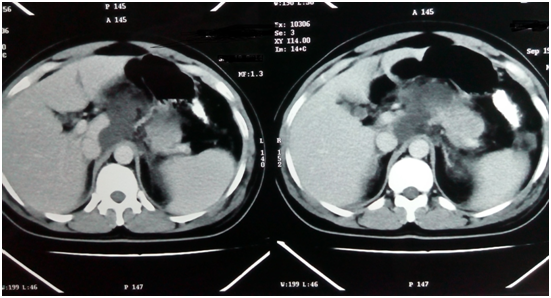

Contrast-enhanced computed tomography (CECT) is the most reliable investigation to diagnose pancreatic necrosis. Necrosis appears as areas of low attenuation (<40 to 50HU) after injecting IV contrast (Figure 1).2 CECT allows accurate assessment of the extent of pancreatic necrosis and peri-pancreatic fluid collections. A CECT in the initial 3-4days of acute pancreatitis might underestimate or miss the necrosis. Usually, a CECT is advised if there is progressive clinical deterioration on medical management to find out any local complication. Serial CECT scans can also assess the progression of the disease and are an essential adjunct when surgical intervention is needed.2,10 Routine blood investigations reveal an increased hematocrit because of hypovolemia, a raised white cell count with leftward shift denoting the presence of inflammation, infection or both.2,3 Raised serum amylase levels (≥3times the upper limit of normal) are virtually diagnostic of acute pancreatitis.11 However the magnitude of this elevation does not correlate with the severity of disease. The levels rise within 2 to 12hours of onset of symptoms and remain elevated up to 6days thereafter. Urinary amylase levels however, remain elevated for a relatively longer duration, being helpful in the diagnosis of patients who report a long time after the onset of symptoms. Serum lipase levels are also raised even after the serum amylase levels have returned to baseline. An ideal laboratory test for evaluation of acute pancreatitis (AP) should, in addition to accurately establishing the diagnosis, provide early assessment of its severity and identify the etiology.11,12 None of the available tests today meet all these criteria. In the diagnosis of AP, serum amylase and lipase remain important tests. Other enzymes for the diagnosis of AP-C-reactive protein, Phospholipase A2, Polymorph nuclear elastase, Immunoreactive trypsin, Interleukin-6, and Pancreatitis- associated protein are in experimental stage and have no clear role in the diagnosis and assessment of severity of AP.11,12

Figure 1 CT suggestive of pancreatic necrosis.